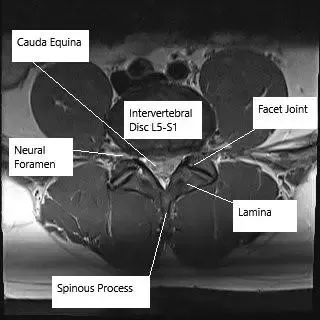

Imagen de resonancia magnética en sección axial que muestra la columna lumbar a nivel de L5-S1.